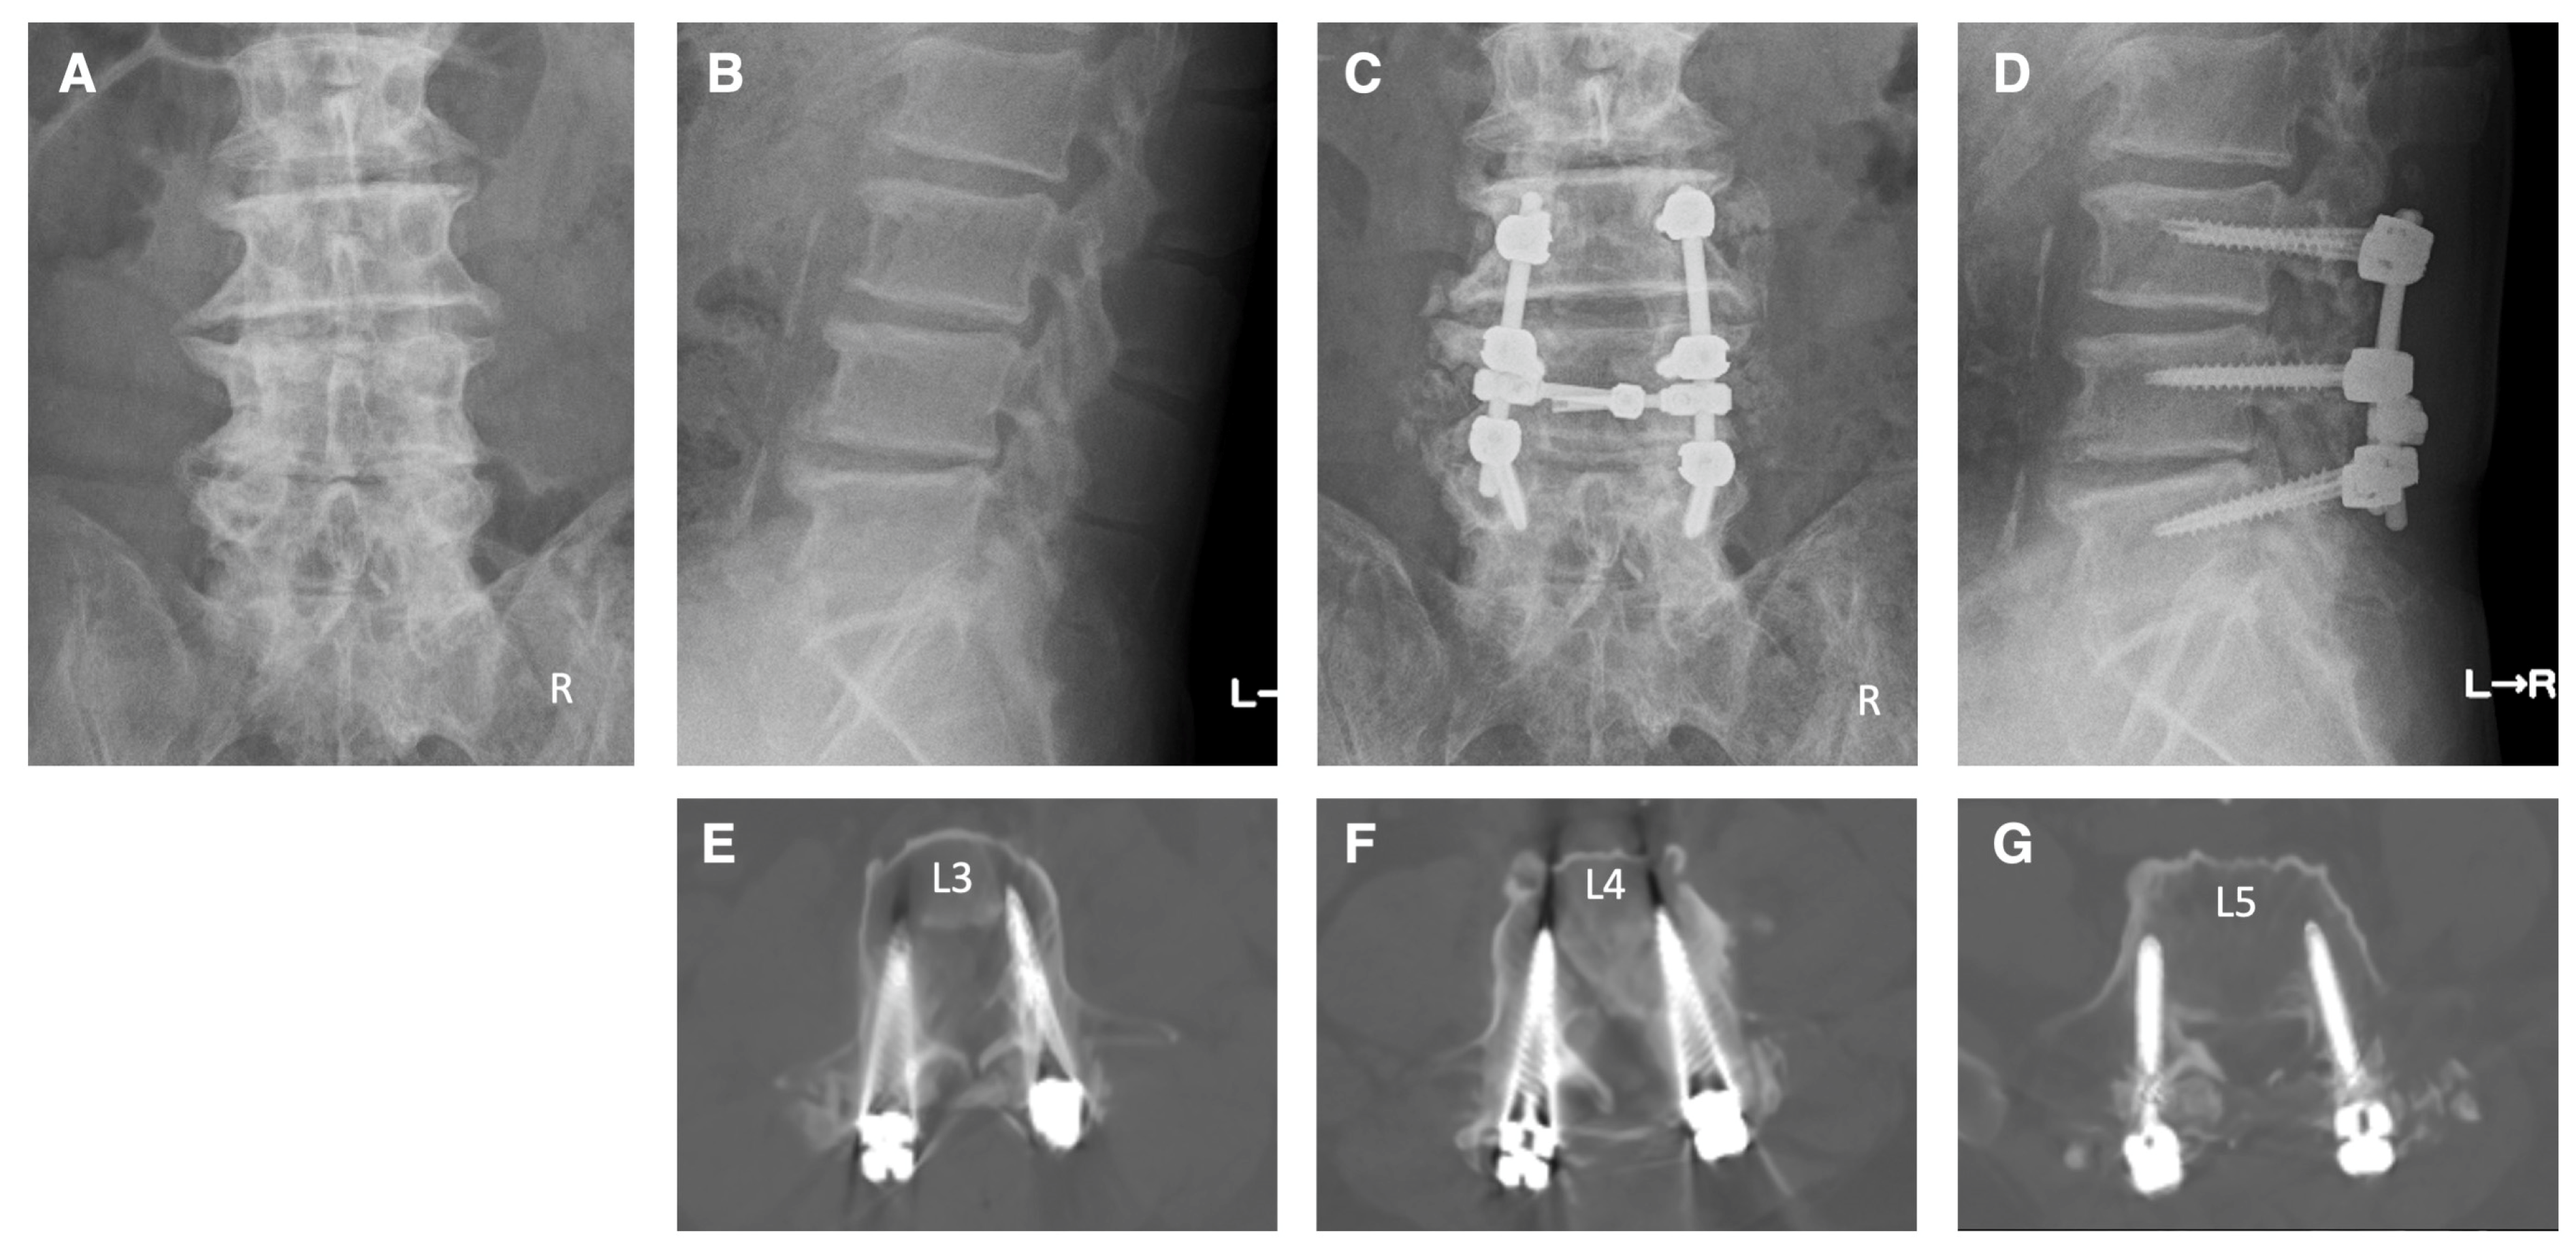

Case 3: A 68-year-old male patient came to our hospital with pain and numbness in his left anterior thigh, as well as intermittent claudication. The patient had a medical history of posterior herniotomy for disc herniation at the L4–5 and L5–S1 levels over 10 years ago. We diagnosed the patient with left L3 and L4 radiculopathies due to spinal canal stenosis at the L2–5 levels and foraminal stenosis on the left side at the L3–5 levels. The patient underwent pedicle screw fixation at the L3–5 levels under navigation. Additionally, posterior decompressions were performed on the spinal canal at levels L2–5 and on the left side foramen at levels L3–5. Postoperative X-ray and CT images indicate that the pedicle screws were properly inserted (Figure 7). Subsequent to the surgery, there was a marked improvement in the pain, numbness, and walking difficulties of the patient.

Figure 7.

Illustrative case 3. (A,B) Preoperative X-ray shows facet joint hypertrophy and spur formation due to degenerative changes at multiple levels in the lumbar spine. (C,D) Postoperative X-ray shows pedicle screw fixation at the L3–5 levels and posterior decompression at L2–5 levels. (E–G) Postoperative CT images show that the pedicle screws were appropriately inserted.